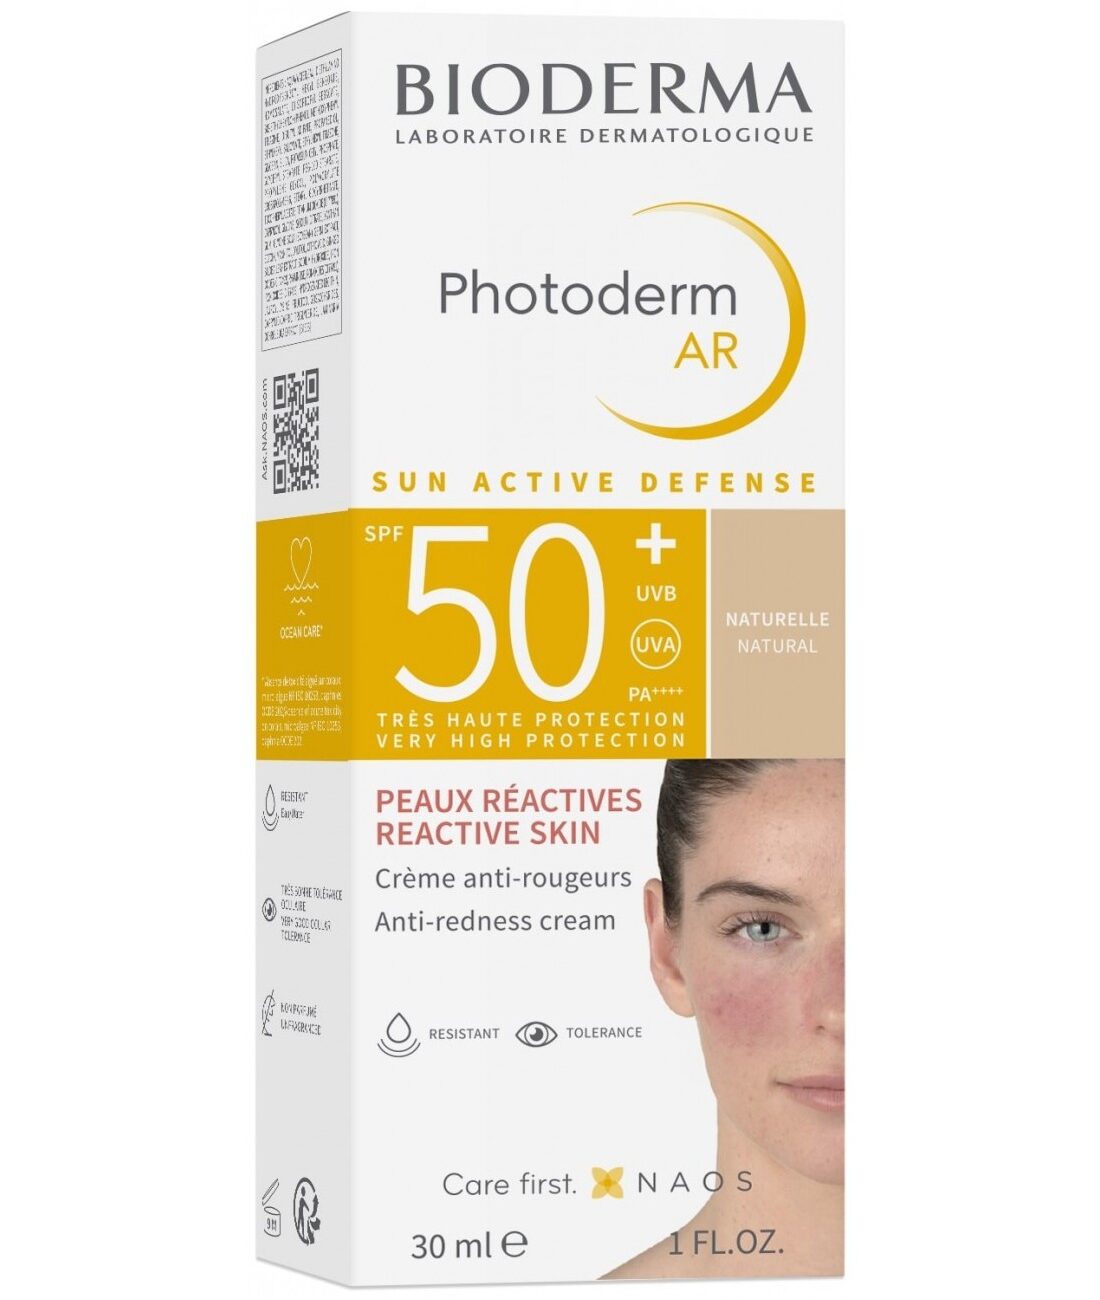

- Nettoyez avec Sébium Gel Moussant ou Sébium H2O

- Appliquez Sébium Sensitive sur le visage en massant délicatement

- Laissez pénétrer avant d’appliquer votre traitement anti-acnéique si nécessaire

- Maquillez-vous directement par-dessus — excellente base de maquillage

💡 Astuce pro : Si vous suivez un traitement dermatologique contre l’acné, appliquez Sébium Sensitive en premier pour créer un film protecteur et maximiser la tolérance cutanée au traitement.